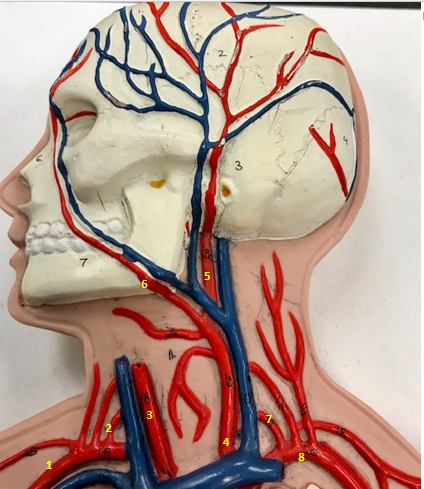

Right subclavian artery

Name #1

Supplies blood to right arm and shoulder

Function of right subclavian artery (1)

Right vertebral artery

Name #2

Supplies blood to brain and spinal cord

Function of right vertebral artery (2)

Right common carotid artery

Name #3

Supplies blood to right neck and head

Function of right common carotid artery (3)

Left common carotid artery

Name #4

Supplies blood to left neck and head

Function of left common carotid artery (4)

Left external carotid artery

Name #5

Supplies blood to face neck and skull

Function left external carotid artery (5)

Left facial artery

Name #6

Supplies blood to face and neck

Function of left facial artery (6)

Left vertebral artery

Name #7

Supplies blood to brain and spinal cord

Function of left vertebral artery (7)

Left subclavian artery

Name #8

Supplies blood to left arm and shoulder

Function of left subclavian artery (8)